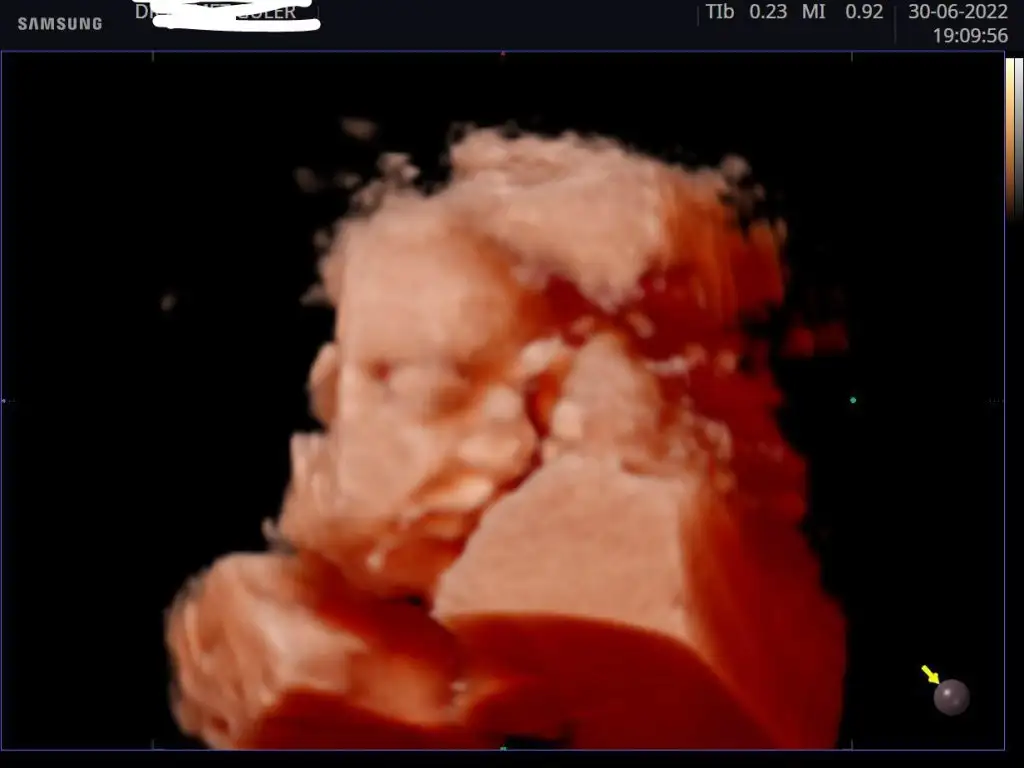

Kontrolümüz güzel geçti, şükür her şey yolunda 🙏🏻 1510 gr olmuşuz 29+5'teyiz. Yine yüzünü tam göstermedi minnoşum, plesantayı yastık gibi kullanıyoruz😬😅

Eklentiler

• IMG_20220630_201019.webp

IMG_20220630_201019.webp

15,2 KB · Görüntüleme: 94

• IMG_20220630_201439.webp

IMG_20220630_201439.webp

15,2 KB · Görüntüleme: 89

Aynen bundan sonra hızlı kilo alımı başlıyormuş. Hep yan profil görebildik, buna da şükür☺️ Bı kaç isim var aklımda ama henüz babasıyla konuşmadım, o da son dakika golü yapmaya çalıştığımı düşünüyor ama ilgisi yok ben karar veremiyorum🙃

Buna da şükür, ağzı yüzü ne güzel belli.isim konusu başlı başına bir iş gerçekten, çocuğun ömür boyu ayrılmaz bir parçası olacak çünkü :)

Evet karar vermek kolay olmuyor☺️ Kiloya göre gününü sormadım, ekranda yazıyor gönderir fotoğrafı diye ama ölçüleri göndermemiş, haftasiyla uyumlu demisti. Senin de bu civarda olur diye düşünüyorum.